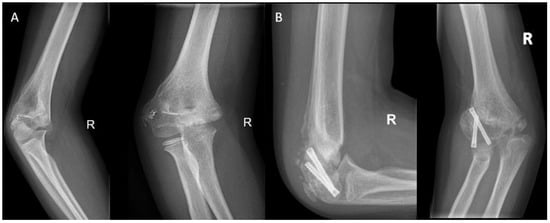

An alternative technique to tether the growth plate is to use transphyseal screws (Figure 7). This technique has a faster correction rate than the tension band principle [56,57]. Hence, this technique may better serve patients that are near skeletal maturity. Soldado et al. [58] used transphyseal crossed cannulated screws (Metaizeau technique) to correct cubitus varus deformities in five very young children. The children had a mean age of 3 years and 7 months and were followed over a mean period of 3 years and 10 months. No correction was observed in all cases. The authors postulated that the ineffectiveness may be explained by the modest growth capacity of the distal humeral physis and because most growth occurs during the pubertal growth spurt, while their follow-up finished before any of their patients reached that stage. Dai et al. [59] studied temporary hemiepiphysiodesis in a total of 135 physes in 66 children with a mean age of 4.69 years old (ranging from 1 to 10 years). In a mean deformity correction period of 13.26 months, 94.06% of the angular deformities were corrected. Thus, posing temporary hemiepiphysiodesis using the Metaizeau technique is an effective method for correcting angular deformities in younger children. A probable reason why the deformity correction for young children in the lower extremity is more successful than in the distal humerus is the difference in axial growth speeds and the percentage of contribution of the physes with regard to the total limb growth. Only 20% of growth takes place in the distal humerus, accounting for a mean of 0.26 cm per year. Conversely, in the distal femur and proximal tibia these percentages are 70% and 60%, respectively, which corresponds to 1.2 cm and 0.9 cm per year [60,61,62].

Figure 7. (A) Elbow radiographs of a 9-year-old girl with a posttraumatic cubitus varus, a flexion deficit of 60 degrees, and avascular necrosis of the medial condyle after a fall from height. (B) An epiphysiodesis using transphyseal screws was performed in addition to an arthrolysis with reduction of the coronoid fossa and release of the ulnar nerve.